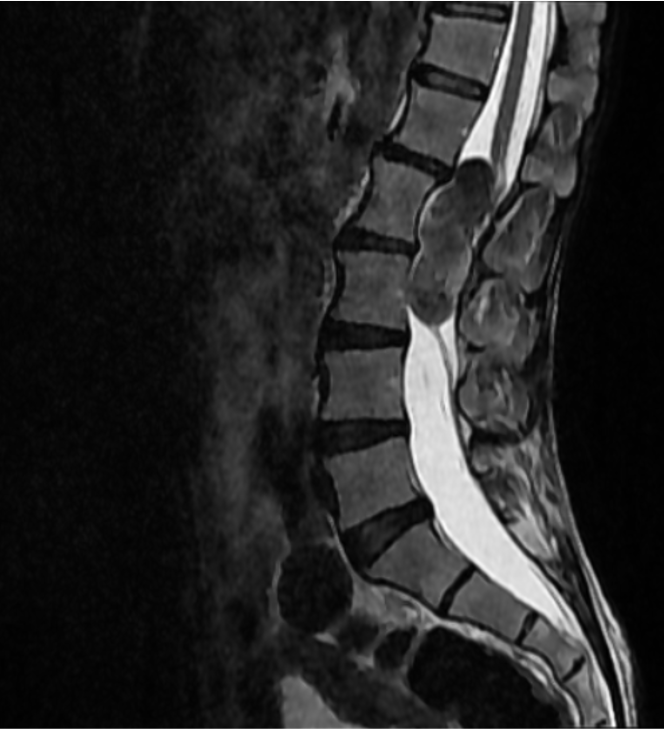

SAGITTAL T2

MRI is the modality of choice for evaluation of spinal epidermoid cysts. Although classically described as T1 hypointense, T2 hyperintense lesions with diffusion restriction, imaging appearances may be variable, particularly in chronic or protein-rich lesions.

In the present case, the lesion demonstrates T1 hyperintensity and T2 hypointensity, an atypical appearance attributed to dense keratinaceous debris, cholesterol crystals, high protein concentration, and chronic desiccation, resulting in shortening of T1 and T2 relaxation times. Such lesions are described as atypical or “white” epidermoid cysts.

Associated scalloping of the lumbar vertebral bodies reflects chronic, slow-growing mass effect, further supporting the benign and indolent nature of the lesion.